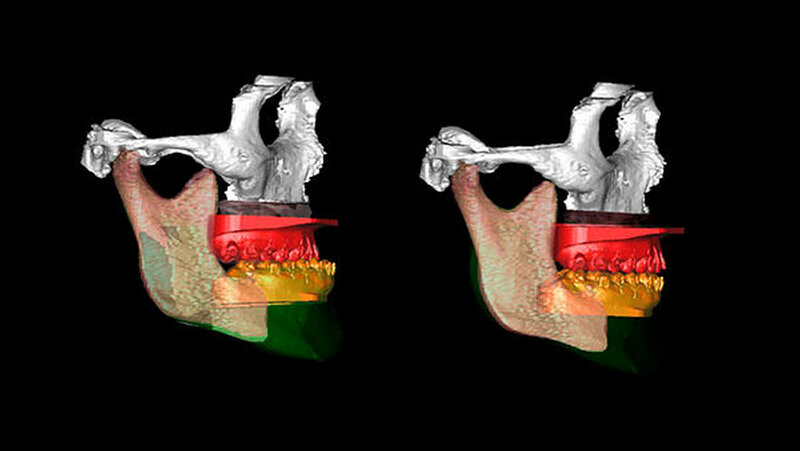

Die Abbildungen 1 und 2 zeigen die klinische Situation bei Erstvorstellung: Der Unterkiefer ist zu prominent. Der Oberkiefer und das Mittelgesicht liegen zurück. In der Front liegt ein umgekehrter Überbiss vor. Der Unterkiefer steht vor dem Oberkiefer. Das erschwert das Abbeißen und Kauen der Nahrung. Die Scans (siehe Abbildungen) dokumentieren, wie aufwendig die virtuelle Operationsplanung erfolgen musste.

Im Dezember 2014 führen die MKG-Chirurgen des Stuttgarter Katharinenhospitals die Umstellung des Ober- und Unterkiefers nach virtueller Chirurgie-Planung durch: Dabei trennen sie den Oberkiefer horizontal vom Gesichtsschädel ab (horizontale Osteotomie in der LeFort Ebene).

Hierzu wird von einem Schnitt im Mund der Oberkieferknochen freigelegt. Mit einer Säge kann ein gezielter Knochenschnitt erfolgen, und nach Präparation wird der Zahn tragende Abschnitt des Oberkiefers vom restlichen Gesichtsschädel gelöst.

Nun muss die Biss-Situation anhand des Computer gefertigten Biss-Schlüssels exakt eingestellt werden, bevor mit zwei Millimeter dicken Osteosyntheseplatten aus Titan der Knochen in der neuen Position mit Hilfe von Titanschrauben fixiert wird. Im Unterkiefer erfolgt die Schnittführung im Zahnfleisch hinter dem letzten Backenzahn beidseits. Nun wird der Unterkiefer mit spezieller Technik durchtrennt. Dies erlaubt eine Verschiebung der Zahn tragenden Basis vom Gelenk tragenden Knochenabschnitt des Unterkiefers.

Bei der Präparation wird der im Unterkieferknochen verlaufende Nervus alveolaris sorgfältig geschont. Die neue Position wird mit einem zweiten Biss-Schlüssel, der die endgültige Biss-Situation einstellt, zugeordnet und mit Osteosyntheseplatten und -schrauben gesichert.